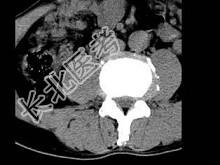

- 单项选择题男,45岁, 腰痛,结合图像, 最可能的诊断是 ( )

A、椎间盘膨出

B、椎间盘突出

C、椎间盘未见异常

D、腰椎骨质增生

E、前纵韧带钙化